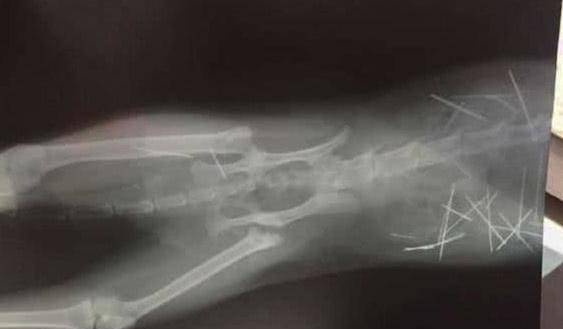

女子感觉相当奇怪,于是就带猫咪去宠物医院做检查,怕猫咪的身体有其他毛病。在宠物医院里,医生给猫咪做了一个x光的外景拍摄,发现了一个很极为恐怖的事情,把女子和医生一众人都吓,原来猫咪身体里有很多的针,那些针密密麻麻爬满它的身体,这个表面上但却很健康最好的猫咪,每天晚上都要能够承受那些个因为自己的五脏六腑的伤害,它在这一瞬间活动,每个动作,都会让自己无比疼痛。

看见自己的猫咪给予如此样的折磨,不由得都流泪了,另外也感觉到很惊诧,要知道这样的场景自己也就没看到过。不知道是什么好人这般如此狠心,对一个猫咪下此毒手。而后医院对猫咪并且了手术,这次手术经历了四个多小时,在医生的精挑细选手术下,将这一根根的针所有去除,这些过程很漫长而艰辛,猫咪也有过住了那样的难过的折磨。